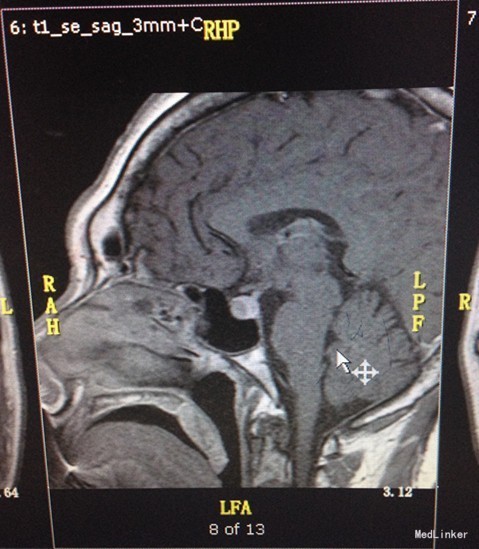

入院查体:口唇增厚,牙列增宽,牙齿稀疏,全身皮肤粗糙、粘膜无黄染及出血点,颈软,左侧甲状腺已切除,可见长约5cm的手术瘢痕,右侧无肿大。 辅助检查, 2015-09-22 08:08 oGTT+胰岛功能: 0分 30分 60分 120分 180分 血糖(mmol/L) 5.67 9.34 11.51 8.16 6.51 胰岛素(mIU/L) 20.77 55.12 148.90 35.43 65.24 C肽(pmmol/L) 1038.472 1957.37 3635.73 3194.84 2571.01 2015-09-22 08:08 葡萄糖抑制试验: 0分 30分 60分 120分 180分 血糖(mmol/L) 5.67 9.34 11.51 8.16 6.51 IGF-1(ng/ml) 1131.00 1196.00 1326.00 1259.00 1002.00 GRH(mIU/L) 32.10 22.80 27.10 23.00 26.00 促性腺激素系列:血清促卵泡刺激素测定FSH35.70mIU/mL,血清促黄体生成素测定LH14.30mIU/mL。血清泌乳素测定PRL257.00mIU/L。尿常规:白细胞每高倍视野JJWBC31.89/HPF,上皮细胞每高倍视野JJEC2.67/HPF,白细胞WBC175.40/uL,上皮细胞 EC14.70/uL。垂体MR平扫+增强:蝶鞍扩大,鞍底下陷,垂体形态饱满,体积增大,垂体右侧T2信号减低,增强后病灶轻度强化,低于正常垂体组织,大小约为1.4x0.8x1.2cm(左右x上下x前后),垂体柄略向左偏移,双侧视交叉略上抬,双侧颈内动脉虹吸部走行正常。诊断意见:鞍区占位性病变,垂体腺瘤可能大,请结合临床。颅脑CT平扫(64排):脑CT未见异常。